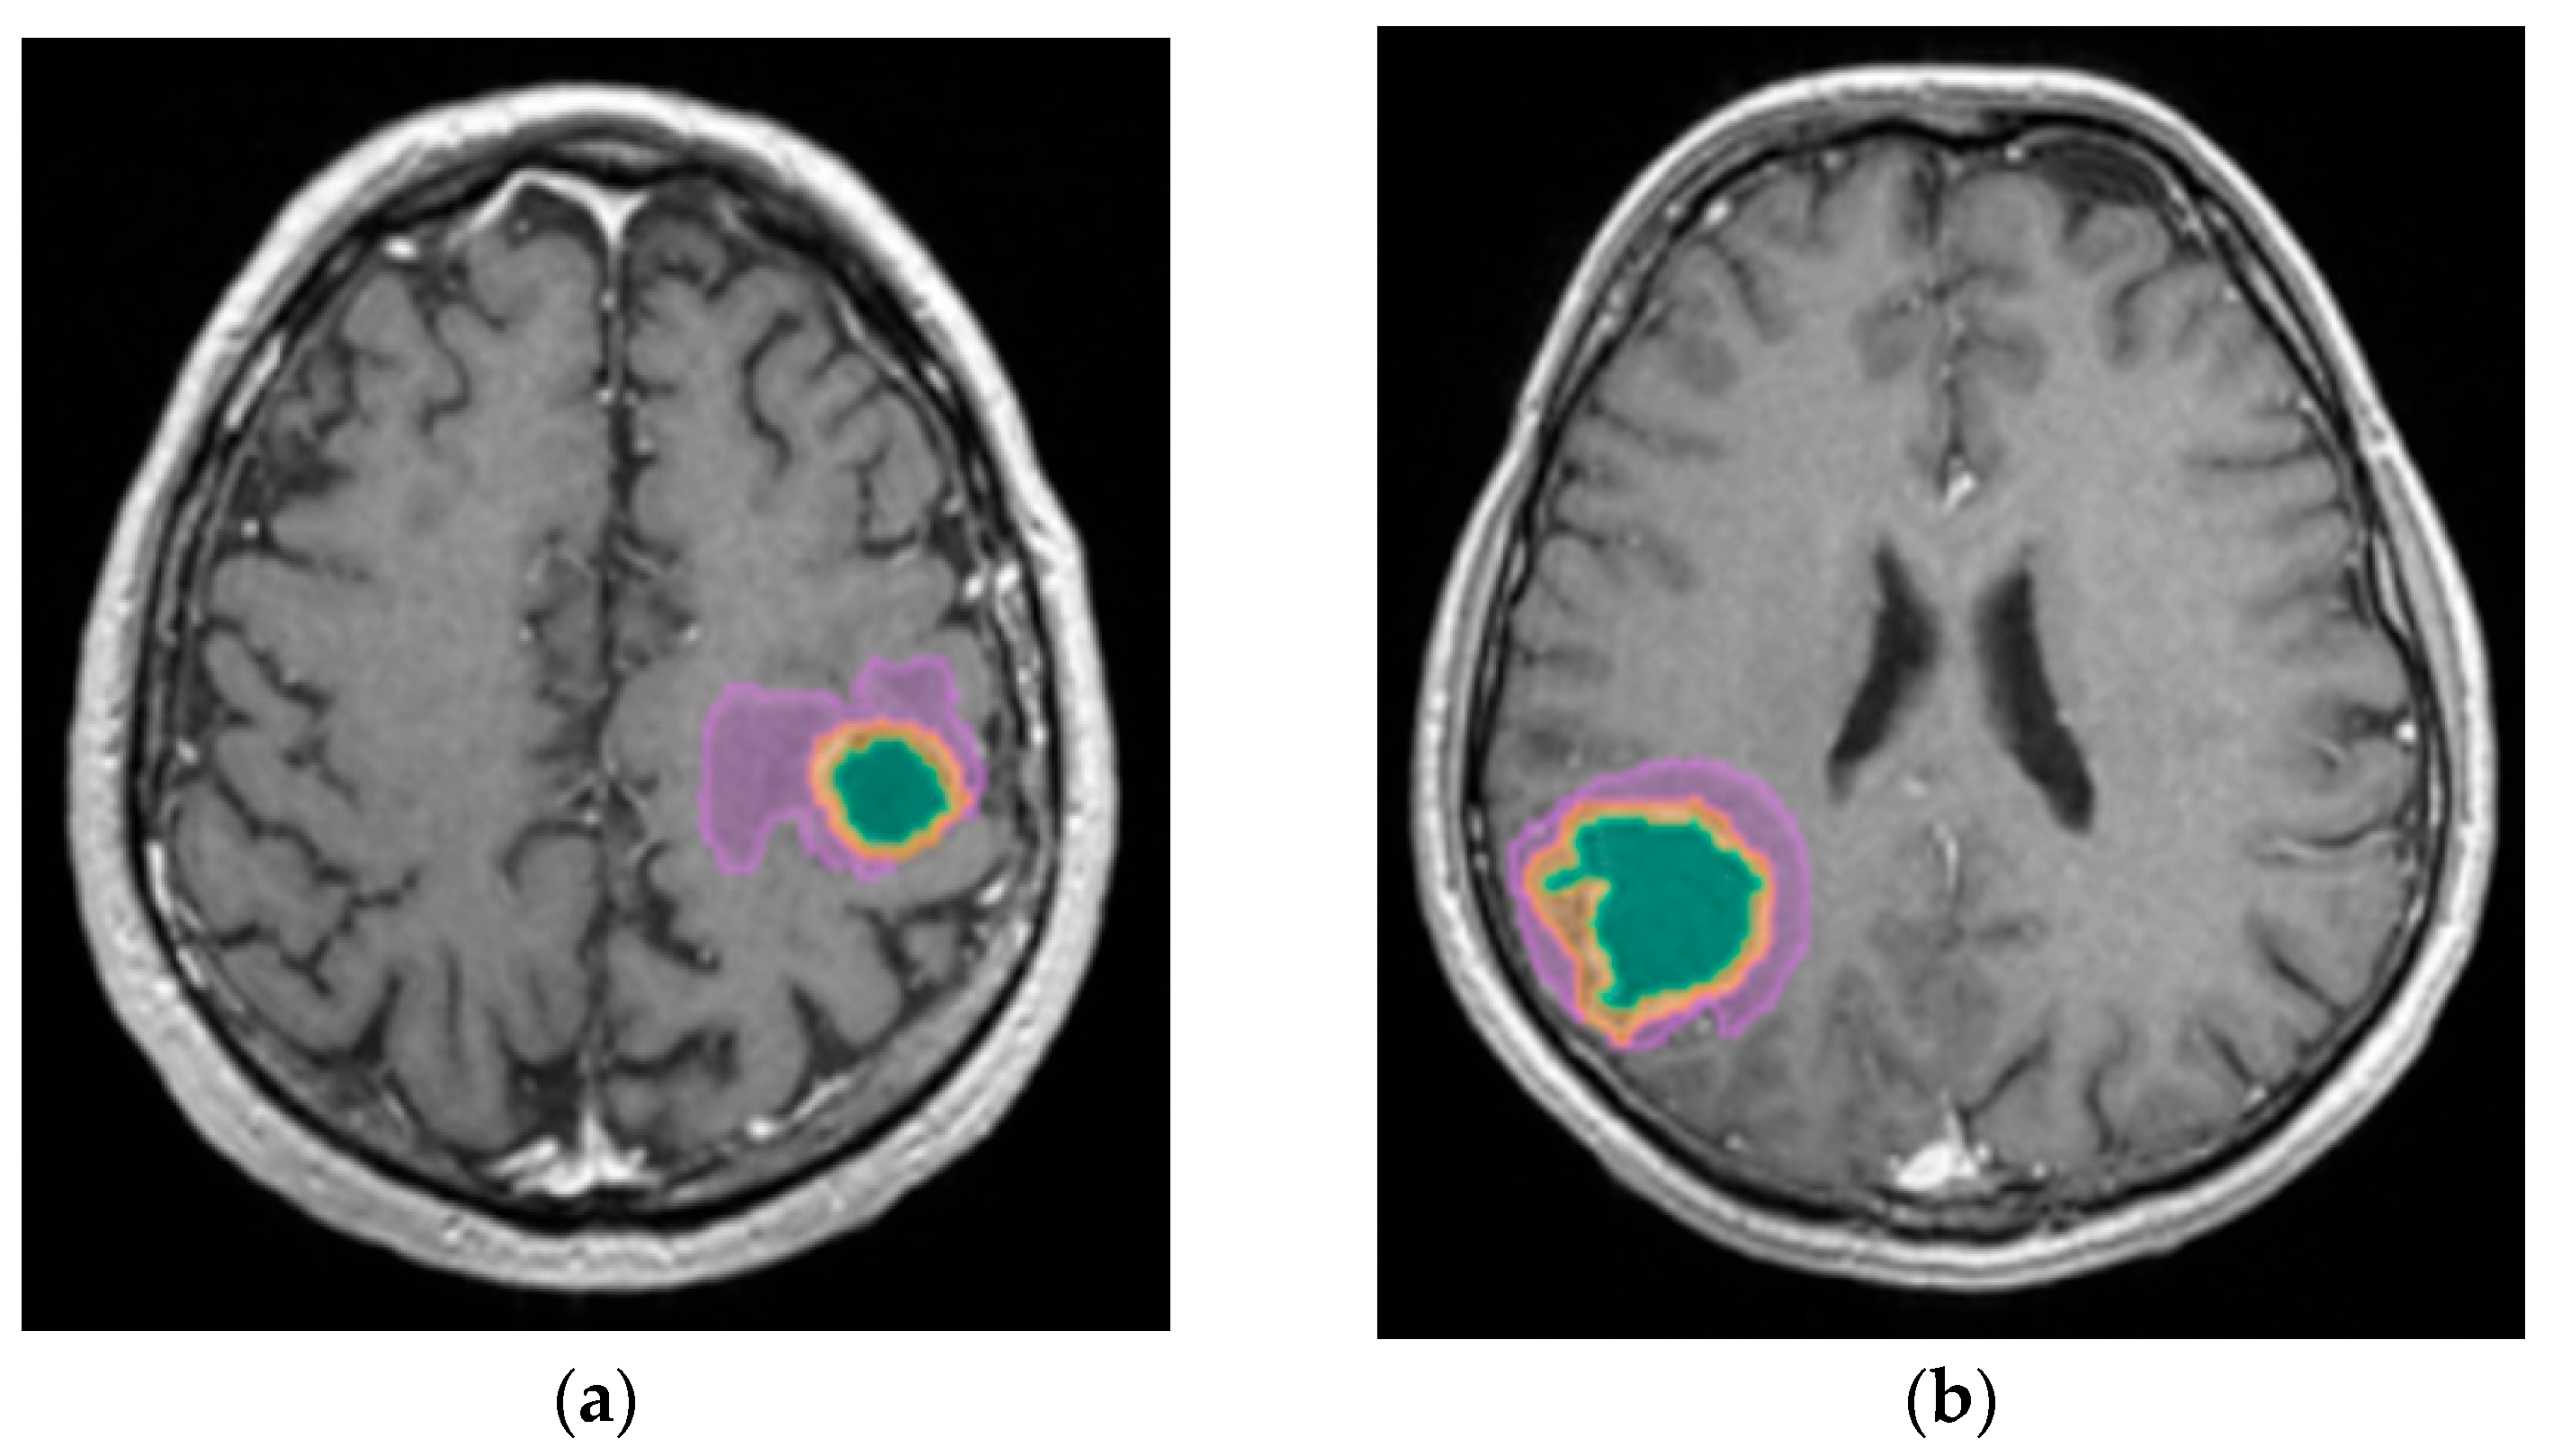

2.4. Automated Segmentation